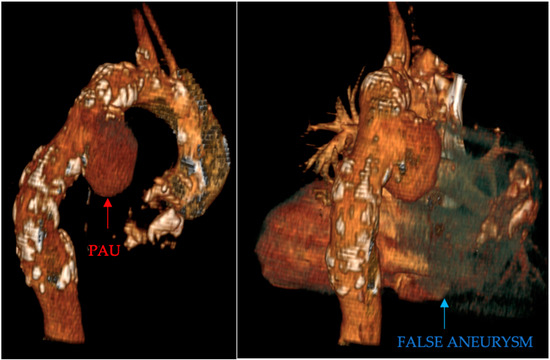

- Penetrating aortic ulcer ruptured: As seen in Figure 2, the thoracic angio-CT scan identified a penetrating ulcer within the aortic wall, particularly located in the isthmic region, measuring approximately 4.2 cm × 3.5 cm. This was a concealed source of significant concern, as it posed an imminent risk of catastrophic hemorrhage.

- Right pleural aortic false aneurysm (Figure 3): The most striking feature was the presence of an expansive false aneurysm within the right pleural cavity, measuring approximately 12.92 cm × 9.3 cm. The size and location of this pseudoaneurysm were unprecedented, introducing a challenge in terms of diagnosis and intervention.